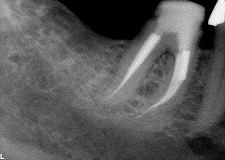

Change is a significant evolutionary tool provided it rests upon a solid and secure foundation. Innovations in materials and technologies occurring within the dental field are impacting powerfully on its art and science; however, dentistry, like all health care, is both a business and a profession. The pendulum swings that predicate trends and transitions within … Read more